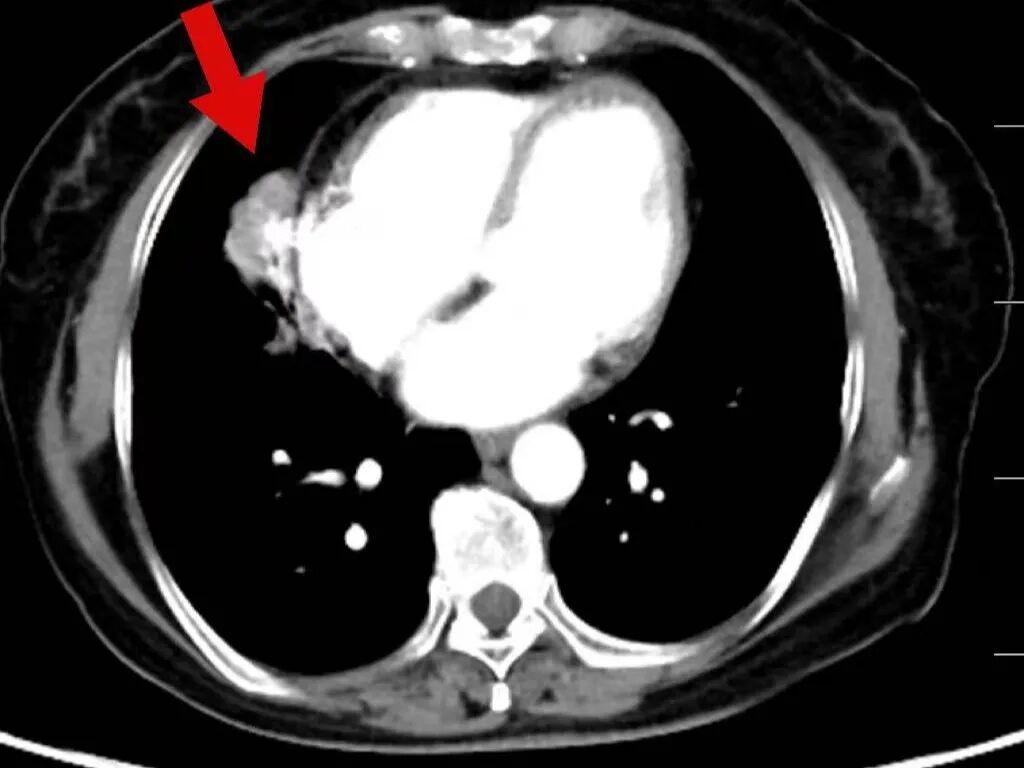

2025年3月17日,肿瘤诊疗中心团队首次为毕女士成功实施BACE治疗。术后患者病情暂时稳定,但5月10日复查显示肺部原发病灶稳定,肝脏转移病灶再次增大。

令人鼓舞的是,治疗一个月后复查显示,毕女士肺部和肝脏的肿瘤明显缩小,病情得到有效控制,生活质量显著改善。出院时,毕女士激动地说:“本来以为病情已经没希望了,是中山医院的专家们没放弃我,一次次调整方案,现在我不仅不怎么难受了,还能正常生活,真的太感谢他们了!

在玉溪市中山医院肿瘤诊疗中心治疗后,肿瘤在明显缩小